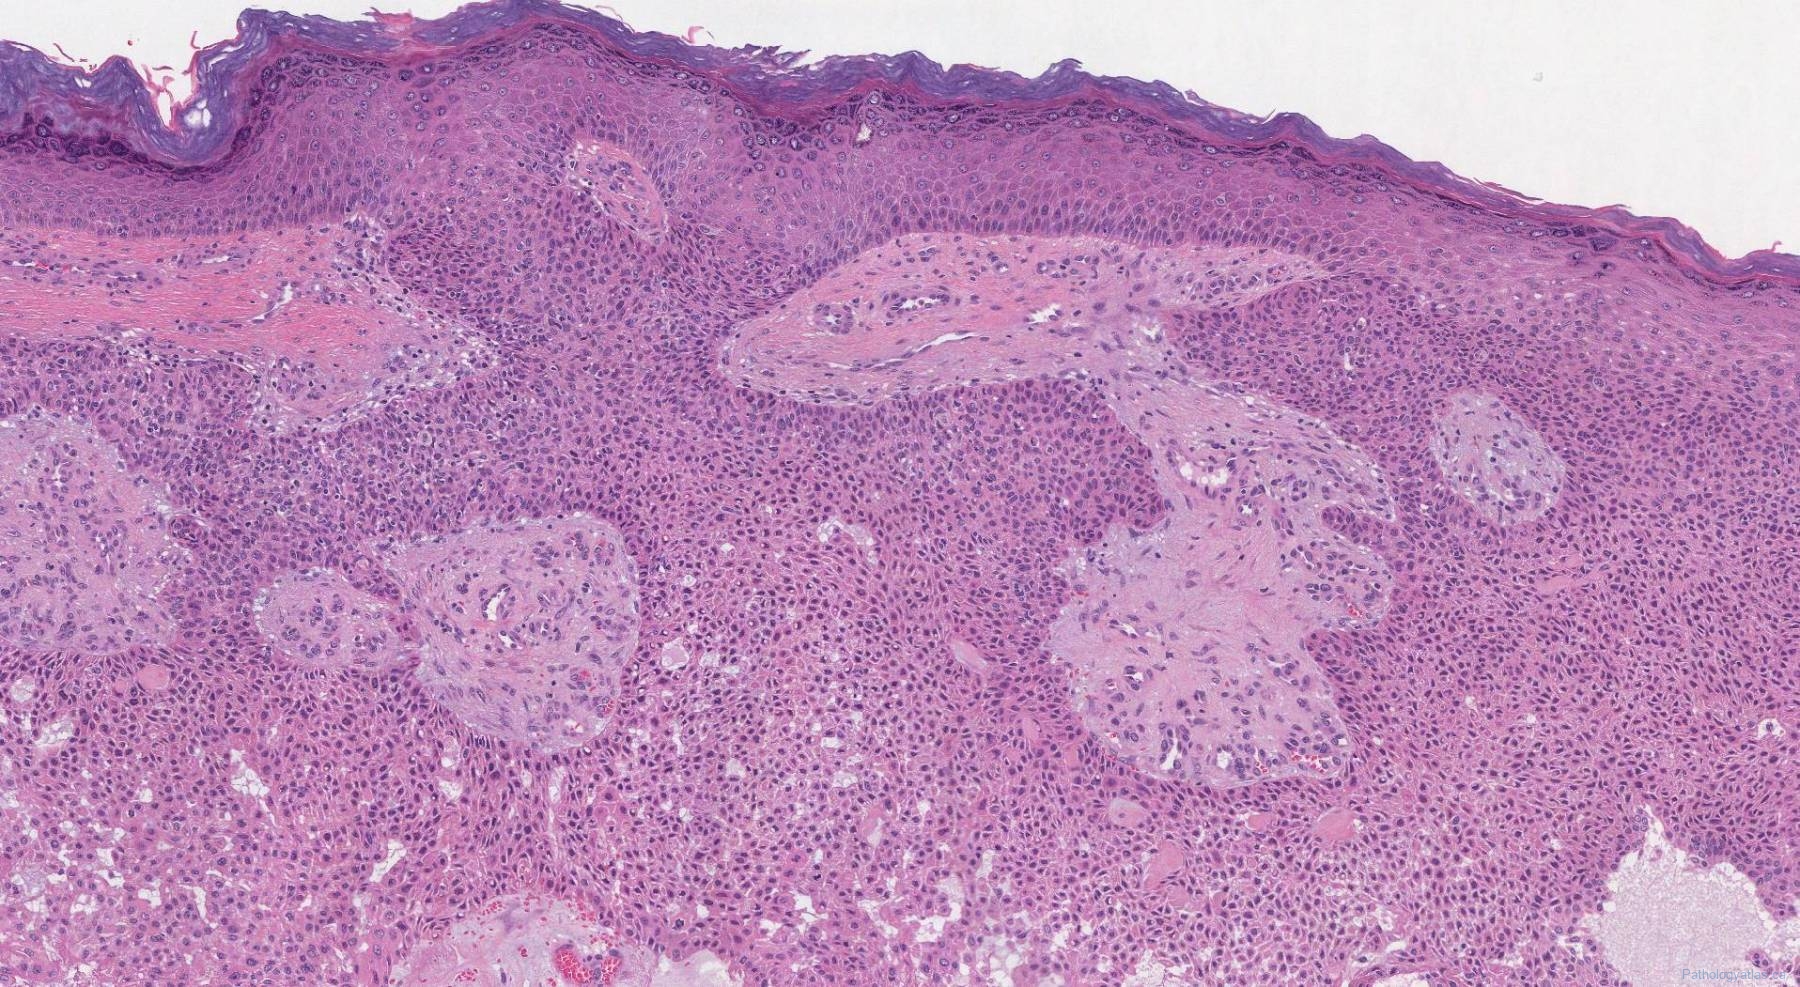

Eccrine poroma